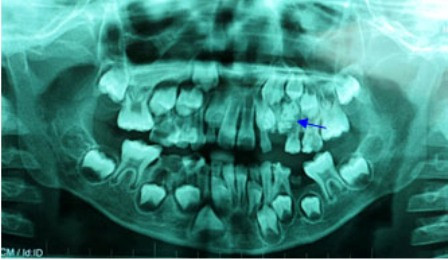

| Hình ảnh X-Quang cho thấy túi răng nằm trong miệng bệnh nhi |

Bệnh nhi được tiến hành chụp phim X-quang để khảo sát, bác sĩ phát hiện có một khối cản quang ở vùng xương hàm trên bên trái, nằm cạnh khối u là chiếc răng nanh sữa. Qua kết quả trên, bác sĩ chẩn đoán bệnh nhân bị u răng, khối u nằm choán hết đường di chuyển của răng nanh sữa và chắn ngang đường mọc lên của hai răng vĩnh viễn số 3 và số 4.